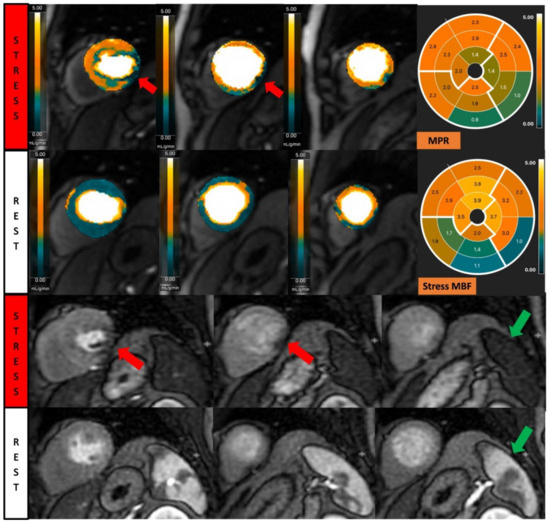

Dynamic contrast-enhanced perfusion imaging is the basic technique of this exam, which captures the signal changes of contrast passing through the chambers of the heart and myocardium. This method uses electrocardiogram-gated fast T1-sensitive imaging and can be performed both during stress and rest [12]. Typical perfusion sequences used are saturation-recovery with balanced steady-state free precession (SSFP), gradient echo (GRE), or GRE-echo planar hybrid readout. Slice thickness is typically 8–10 mm with temporal resolution around 100–125 ms, usually acquiring every heartbeat, but acquired across two heartbeats in higher heart rates. Myocardial ischemia is assessed during vasodilation, which is commonly induced by injecting adenosine, dipyridamole, regadenoson, or adenosine triphosphate (ATP) [13]. Gadolinium-based contrast is then injected (0.05–0.1 mmol/kg, 3–7 mL/s), followed by a saline flush (≥30 mL) into a peripheral vein after achieving hyperemia to visualise the trajectory of blood flow and myocardial perfusion supplied by normal coronary arteries versus diseased vessels. Ischemic myocardium therefore shows slower perfusion and a decreased T1 signal when compared to normal segments (Figure 1).

Figure 1.

Stress perfusion showing myocardial ischemia using adenosine. Upper and lower panel shows a single basal ventricular short axis slice acquired during stress perfusion imaging. The gadolinium contrast first enters the right ventricle, then the left ventricle, and finally perfuses the myocardium. Red arrow shows myocardial ischemia in the basal anteroseptal wall with decreased T1 signal compared with normal segments.